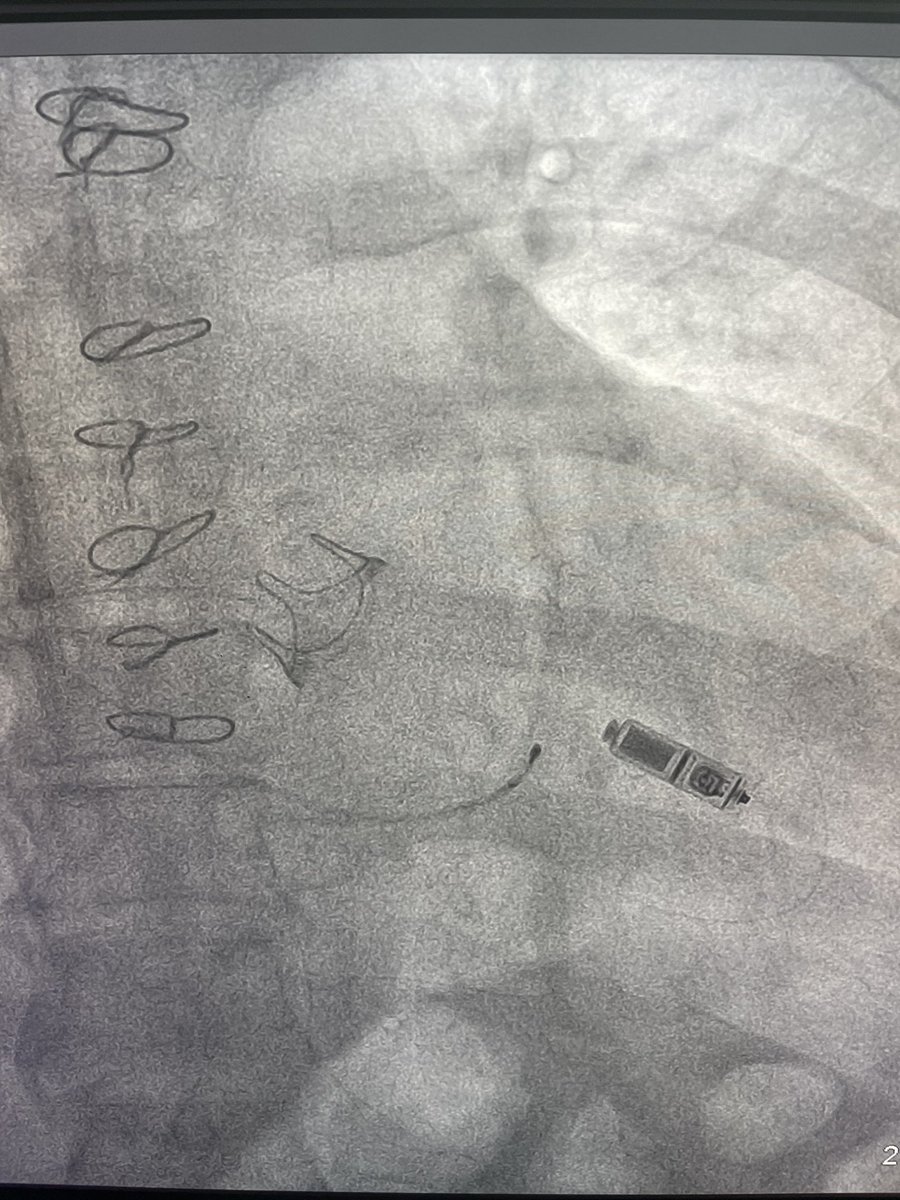

Always loving collaboration with my buddy @FellowEP . Today we did, to the best of our knowledge, the first ISP-LV access in Chile. To tackle a VT storm with mechanical AV and MV. @hhuang123 @DrRoderickTung @Dr_Santangeli @andresenriqueza @ABeaser @gauravaupadhyay